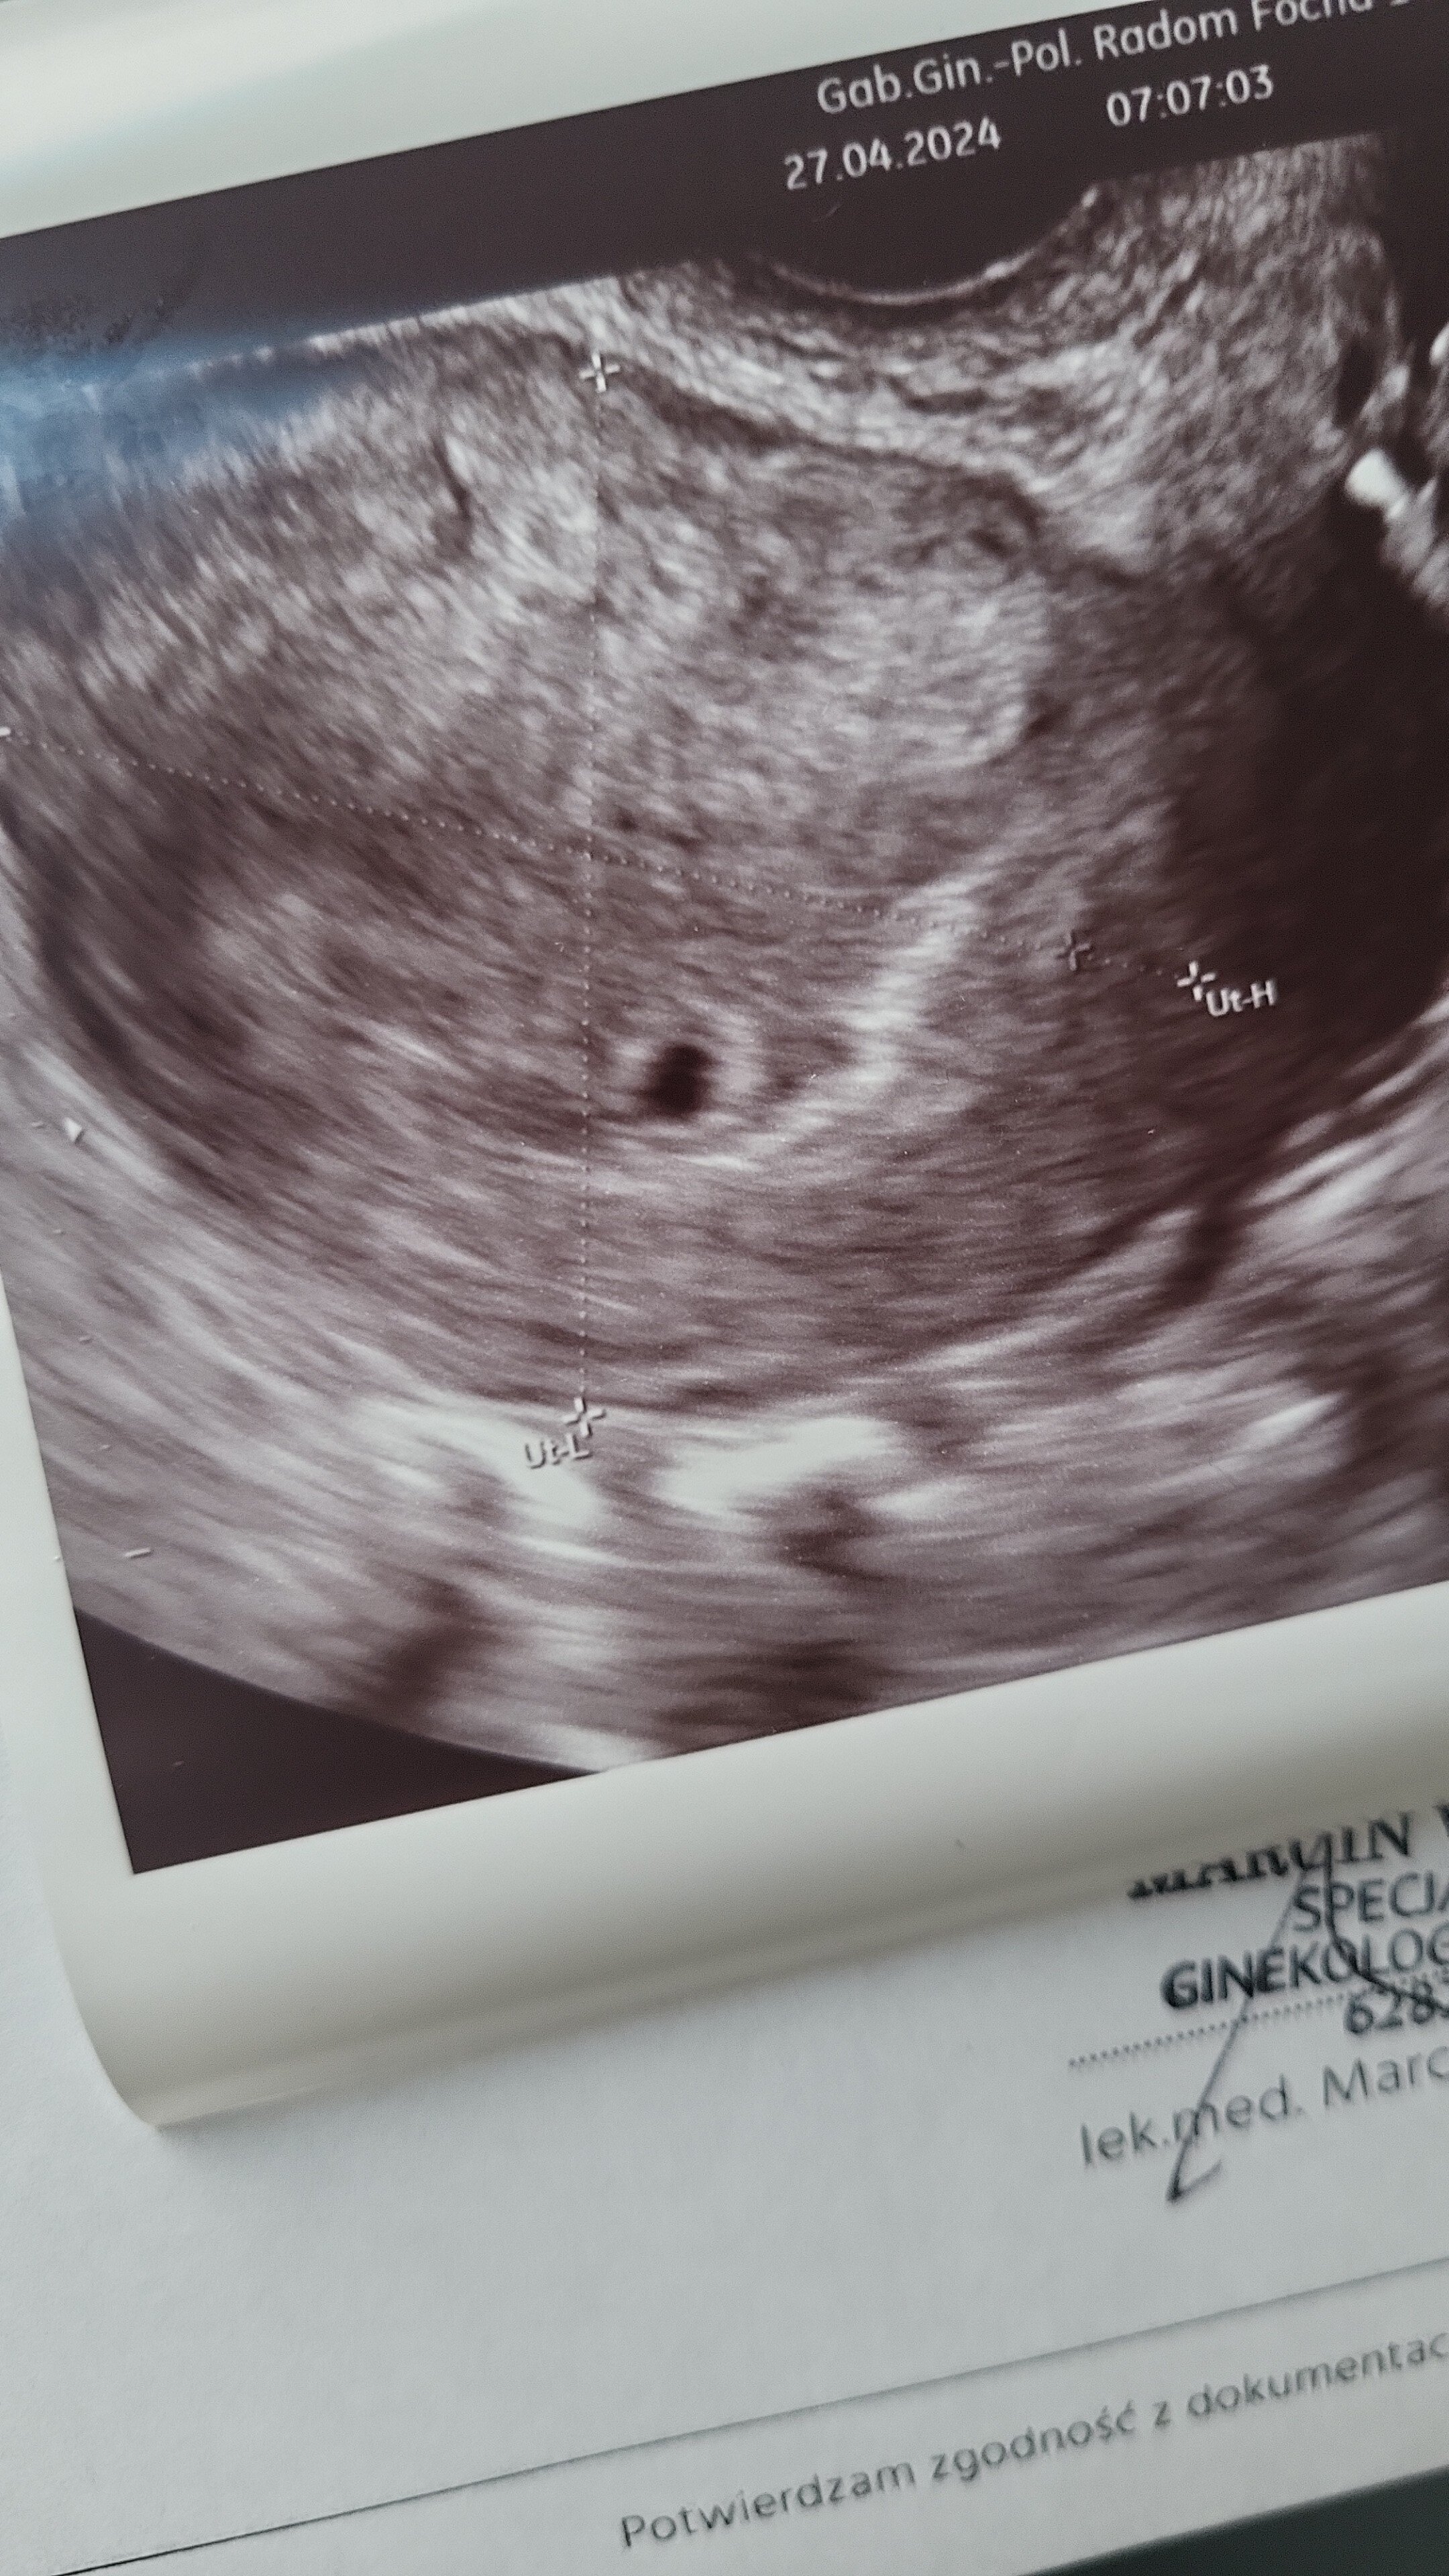

Hej dziewczynki, ale się rozpisalyscie🙂Kurcze ja to przy mojej dwójce szogunkow nie mam na nic czasu😉byłam dziś na wizycie🙂miałam isc później, ale stwierdziłam że chce się uspokoić ze jest zagniozdzona w macicy..I jest🤩lekarz już nie kazal robić drugiej bety bo mówi że już pęcherzyk ładnie widać więc spokojnie i dal skierowania na różne badania🙂do mnie to ciągle nie dociera😛Widzę że u Was to już niektóre 9 tydzień maja🙂Wow🙂u mnie dopiero 5 tydzień 🙂co do cery to u mnie pięknie i to właśnie był jeden z obajawow ciazy, bo zawsze przed okresem mam jedną wielką kroste🙂a teraz jej nie miałam i w poprzednich ciążach też tak bylo😅

• IMG-20240427-WA0000.jpeg

IMG-20240427-WA0000.jpeg

1,5 MB · Wyświetleń: 84